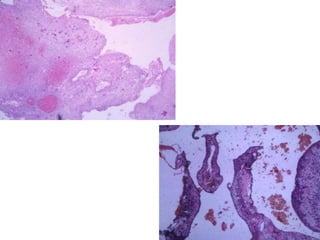

• Microscopy-

• The proliferating Langerhan’s cells are ovoid/round,

histiocyte like cells, 10-15 um in diameter that are

arranged in aggregates, sheets or within loose

fibrous stroma.

• Cells have eosinophilic cytoplasm and contain

central, ovoid coffee bean shaped nuclei.

• Coffee bean appearance is produced by deep

indentations, clefts and folds of the nuclear

membranes which form linear grooves that traverse

the length of the nuclei.

• Most of the Langerhan’s cells are mononuclear but

some cells contain multiple nuclei, which tend to be

centrally located.

• Accompanying infiltrate of eosinophils which may be

so dense that it obscures underlying Langerhan’s

cells.

• Lymphocytes, plasma cells, macrophages,

neutrophils, osteoclast-type giant cells can also be

seen.

• Necrosis if prominent is usually a complication of a

pathologic fracture.

• Langerhans cells strongly express CD1a and S-100

Langerhans’ cell histiocytosis.

Polymorphic appearance resulting from an admixture of Langerhans’

cells, nonspecific histiocytes, lymphocytes, and eosinophils. There is a

mild atypia in the Langerhans’ cells that can simulate a malignant

process.